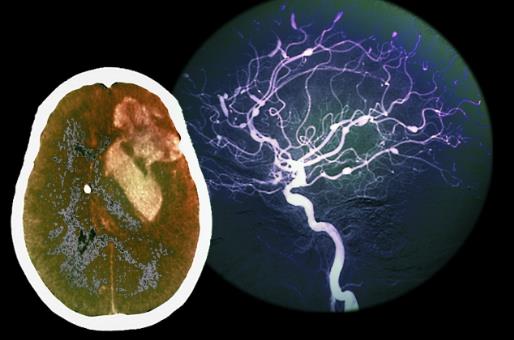

心脏:从40岁开始老化

随着我们的身体日益变老,心脏向全身输送血液的效率也开始降低,这是因为血管逐渐失去弹性,动脉也可能变硬或者变得阻塞,造成这些变化的原因是脂肪在冠状动脉堆积形成:食用过多饱和脂肪。